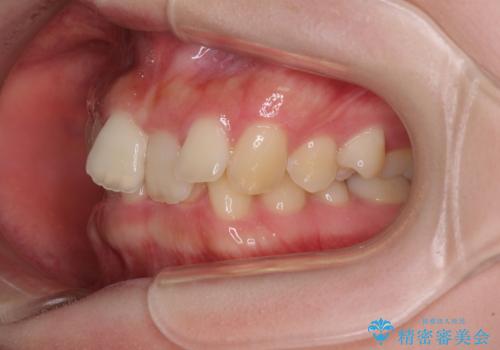

- 全体的な歯列の叢生を気にして来院された患者様です。

奥歯の咬み合わせを見ると、片方は上顎が下顎に対して相対的に前方にあり、他方は交叉した咬合の状態でした。

咬み合わせを改善するためには、上顎臼歯を後方に移動させた咬み合わせにする必要があります。

インビザライン単体で改善することも可能ですが、ディープバイトのためインビザライン単体で達成する可能性が低いと考えられたため、カリエール・ディスタライザーという補助装置を併用して、より確実性を上げることとしました。

カリエール・ディスタライザーを使用している期間、反対側はワイヤー矯正により叢生を解消していくこととしました。